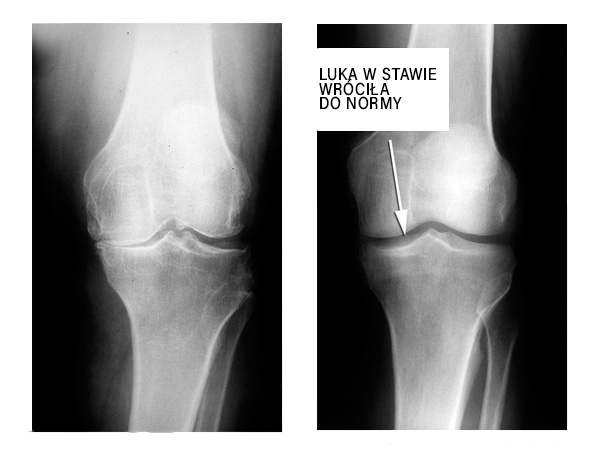

Na tym zdjęciu rentgenowskim chcę pokazać efekt działania preparatu Cannabis Oil. Odbudowa uszkodzonego stawu po zastosowaniu kuracji kapsułkami Cannabis Oil: